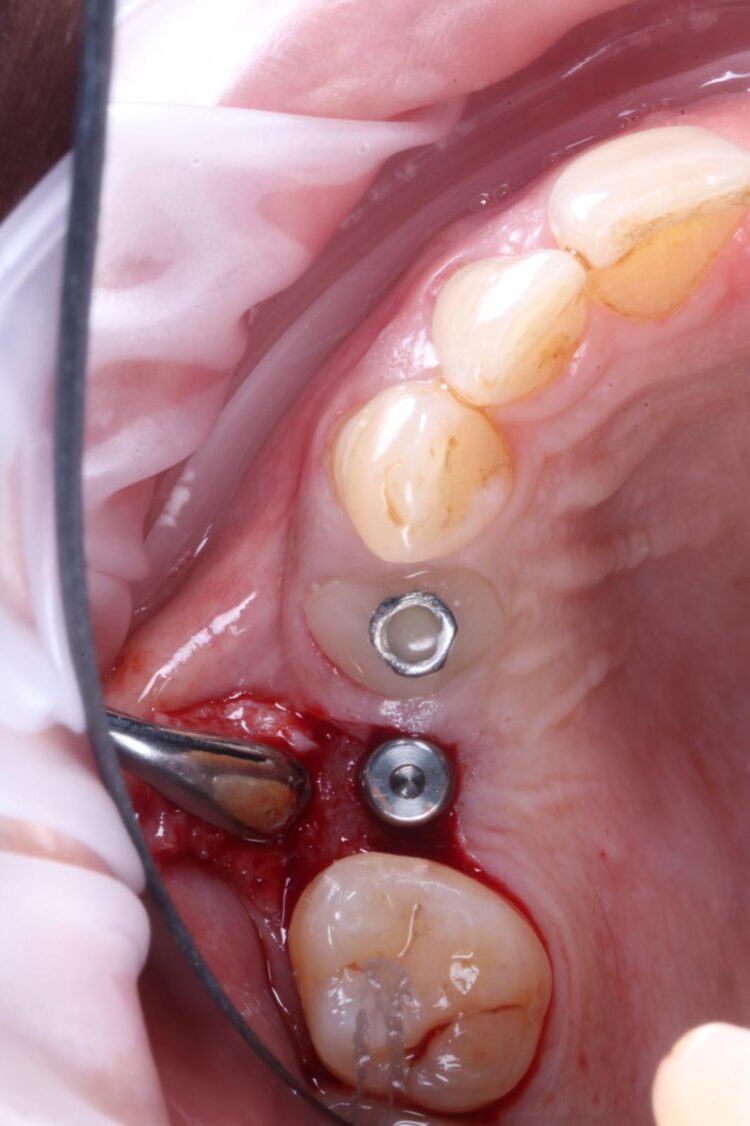

The UL4 root was extracted as atraumatically as possible. The roots were thin and spindly, and needed to be split to be removed safely. They were sectioned in a mesial-distal direction to leave the buccal and palatal roots separate, reducing the risk of fracture and preserving the interdental and surrounding bone.

A flap was raised in the UL5 site using a paracrestal incision – vertical incisions were avoided to preserve blood supply to the gingiva, protecting the papilla between the UL6/7 for optimal aesthetic and soft tissue outcomes.

The surgical guide was then placed in the mouth and the manufacturer’s specific drilling sequence followed, increasing the osteotomy in size incrementally.

Two 3.8mm diameter CONELOG® Progressive-Line implants were placed through the guide, following the plan precisely. The UL4 implant was longer (11mm) to ensure sufficient apical bone was engaged for primary stability, it was also positioned in the palatal root to ensure good engagement with the bone and better bone to implant contact. A sizable jump gap was noted between the implant and the buccal plate of around 5-6mm. From a biological perspective, the jump gap can be left because the ridge would heal to leave a sufficient buccal plate. However, the literature[iv] shows that grafting reduces the amount of bone resorption post implant placement, which was one of the reasons that augmentation was indicated in this case.